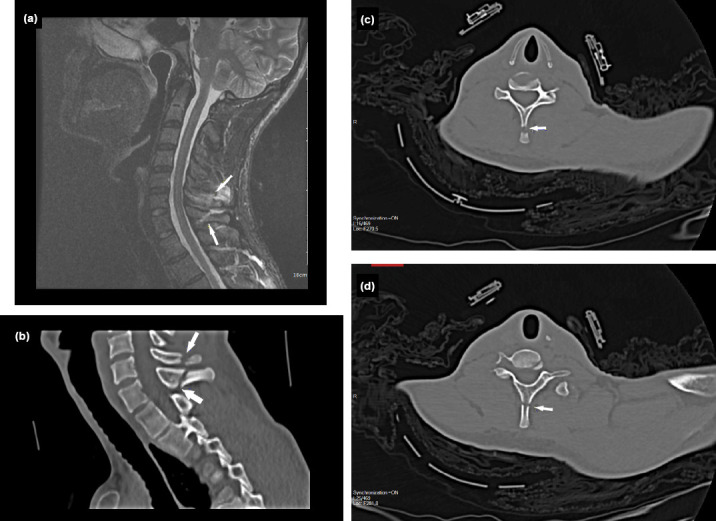

Results: A total of 44 patients (36 men and eight women) were included in the study, with a mean age of 43.1 years. Among them, 25 patients were admitted due to traffic accidents and 18 due to falls. Spinous process fractures were observed in 18, 17, and three patients in the cervical, thoracic, and lumbar regions, respectively. Multiple spinous process fractures were found in 15 patients, while six patients had fractures in both the cervical and thoracic regions (Clay-Shoveler's fracture). In 12 patients, spinal MRI with Short-TI Inversion Recovery (STIR) sequences was performed in addition to CT imaging. All patients with Clay-Shoveler's fracture fractures underwent both CT and MRI examinations. In all cases where MRI was performed, interspinous ligament damage was detected. However, no intracanal involvement or comorbid pathology was observed.

Conclusion: Notably, multiple fractures may occur, particularly at the cervicothoracic junction. Although spinous process fractures associated with trauma are rarely isolated, they are usually managed with medical treatment. Therefore, the vertebrae below the initially detected fracture site should also be evaluated. Additionally, imaging studies such as MRI with STIR sequences should be performed to assess ligament damage and the neural canal, in addition to tests for evaluating bony structures.